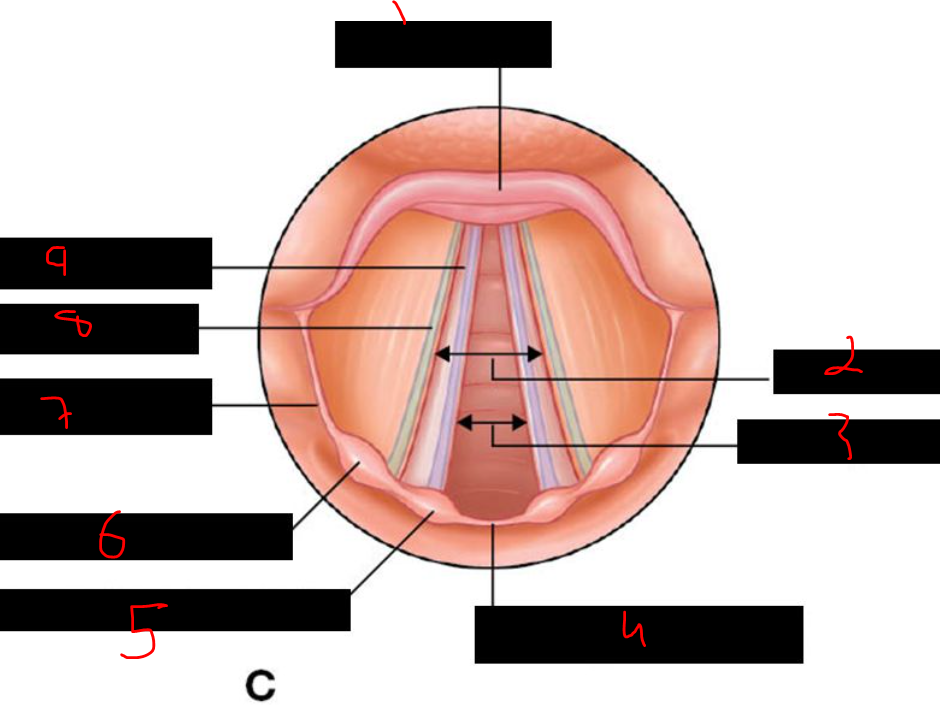

atlas

31

card image

What is 18?

"lateral band"

32

What is 19?

pharyngeal orfice of eustachian tube